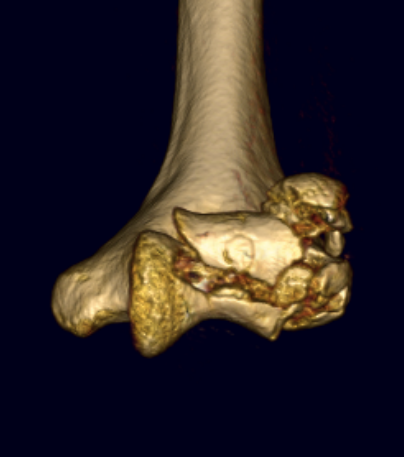

Dubberly Classification

Type I Type Ii Type III

Capitellar fracture

Capitellum + trochlea fracture

In one piece

Capitellum + trochlea fractures

In two separate pieces